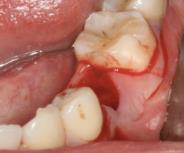

诊断:35牙牙松动。 治疗:拔除患牙,即刻种植。 手术记录:常规消毒铺单,局部浸润麻醉,于35牙牙位行横行切口,骨膜剥离器剥开黏骨膜瓣,显露术野。拔除松动牙,生理盐水冲洗冷却下,球钻定位,植入种植体,旋入愈合帽。 术后拍片,种植体方向好。10天后检查,伤口初步愈合。